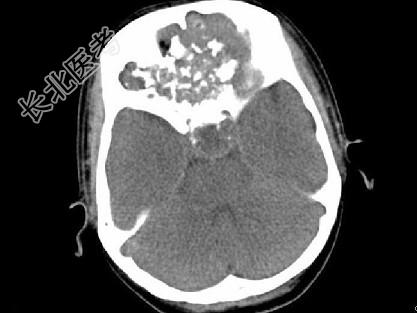

- 单项选择题男,26岁, 进行性鼻腔阻塞、流涕来院就诊,近两年持续性头痛、头晕, 筛窦区病变影像检查如图,最可能的诊断是 ( )